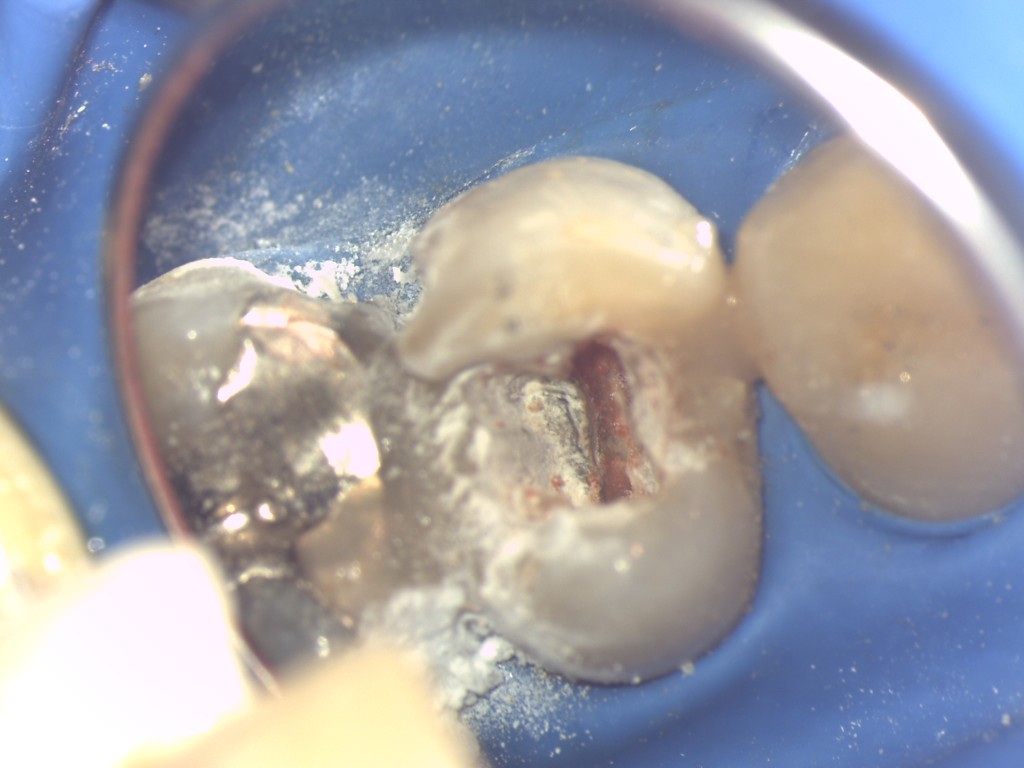

虫歯により歯の手前の壁が崩れているので隔壁を作ることが大切です。

白い樹脂(コンポジットレジン)で壁を作り根管治療の準備が出来ました。写真で赤く見えるのは歯髄(神経・血管)です。